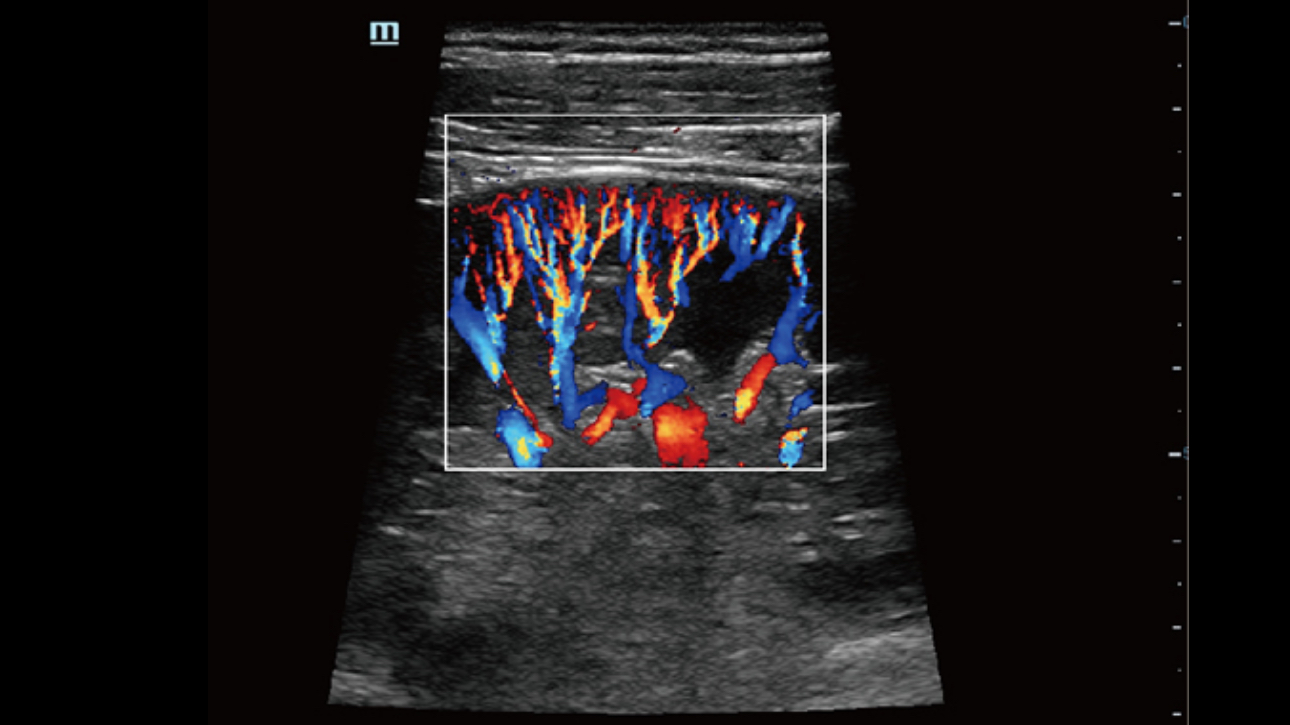

The channel data based ZST+ is an extraordinary innovation, representing an ultrasound evolution. Transforming ultrasound metrics from conventional beamforming to channel data based processing; ZST+ is able to deliver multiple imaging advances: Advanced Acoustic Acquisition, Dynamic Pixel Focusing, Sound Speed Compensation, Enhanced Channel Data Processing and Total Recall Imaging.

By transmitting and receiving a relatively smaller number of large zones, Advanced Acoustic Acquisition extracts more information from each acquisition, 10 times faster than a conventional line-by-line beamforming method.

Channel data based ZST+ provides Enhanced Channel Data Processing for greatly improved imaging clarity. By multiple and retrospective channel data processing, it makes the best use of acoustic information for image improvement.